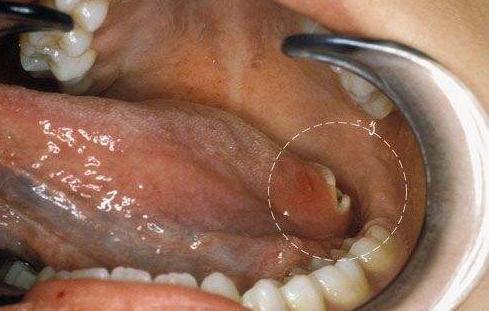

如果你长期吃槟榔,已经出现舌头不灵活,说话口齿不清或嘴张不开的情况,那你就要小心了。

口腔癌 前兆: 口腔溃疡是癌的“保护伞”

在临床上,很多癌患者是因为自觉“口腔溃疡”难愈,疼痛难忍,才决定去医院检查,最终被确诊为口腔癌。通常来讲,口腔溃疡就是口腔癌的前兆。